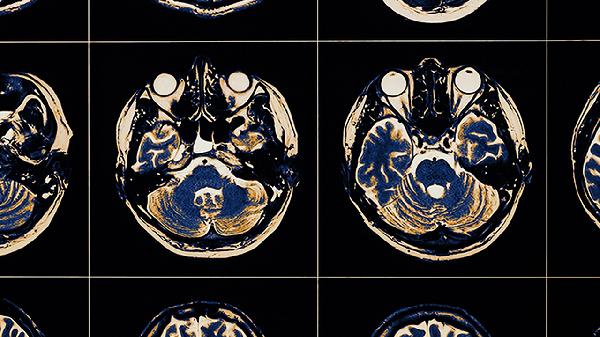

脑血栓患者除规范用药外,需保持低盐低脂饮食,每日钠盐摄入不超过5克,适量食用黑木耳、深海鱼等有助于改善血液循环的食物。康复期可在医生指导下进行肢体功能训练,避免久坐不动。注意监测血压血糖指标,定期复查头颅CT评估治疗效果。出现头痛加剧或意识改变需立即急诊处理。